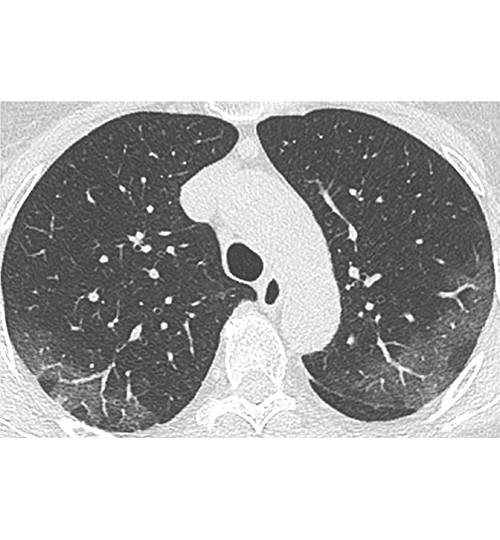

Ce sont essentiellement des plages de verre dépoli non systématisées à prédominance sous-pleurale, et à un stade plus tardif de condensation alvéolaire. Il n'y a en règle pas d'excavations, de nodules ni de masses. Les micronodules bronchiolaires, les adénopathies médiastinales et les épanchements pleuraux sont rares, en sachant que ces derniers sont possibles en cas de décompensation cardiaque.

Image : Tomodensitométrie. Patiente de 71 ans sans antécédent, atteinte de Covid-19 et ayant une pneumopathie interstitielle. Aspect typique initial : atteinte bilatérale à type de verre dépoli périphérique sous-pleural. Crédit : Société française de radiologie.